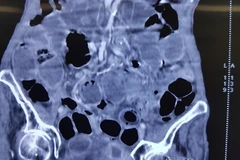

Bệnh nhân có tiền sử sỏi thận đã hai năm, đau lưng trái âm ỉ, kèm bệnh lý huyết áp cao đã nhiều năm, đặc biệt, bệnh nhân đã đặt stent mạch vành ba năm và có điều trị liên tục.